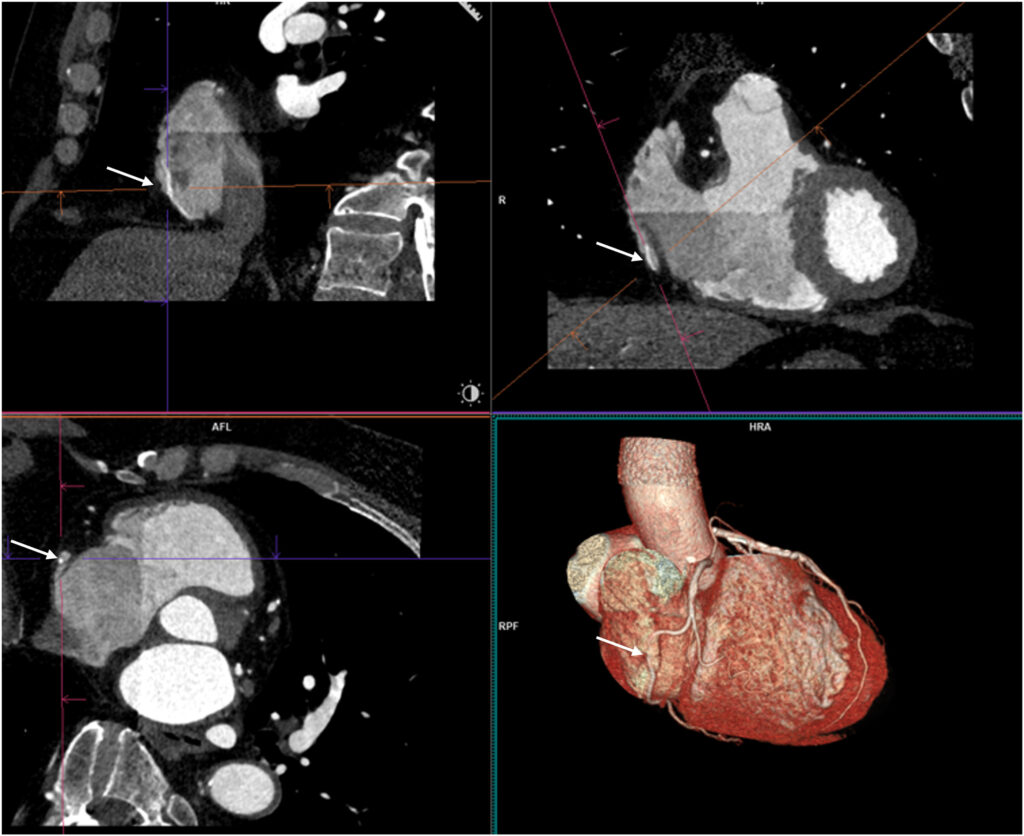

O exame mostrou origens normais tanto da CD quanto da coronária esquerda, com presença de lesão aterosclerótica com estenose moderada na DA, bem como confirmou a suspeita de trajeto anômalo da CD, com o seguimento médio apresentando curso intra-atrial transversal de 3.5 cm.

A reconstrução 3D ilustrou, de forma muito didática, o trajeto intracavitário da coronária direita.

Posteriormente, o paciente foi submetido a cateterismo cardíaco que confirmou a presença de lesão moderada no terço médio da DA enquanto que a CD não apresentava lesões ateroscleróticas. O paciente recebeu alta sob tratamento clínico direcionado.